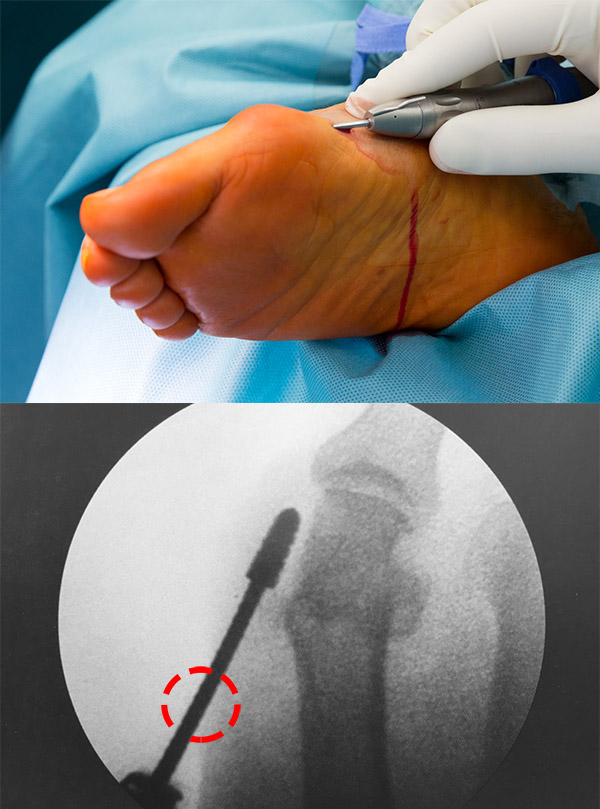

• Die Wahl der Inzisionen ist von entscheidender Wichtigkeit. Liegt der Zugang an einer falschen Stelle, wird die Zielstruktur nicht, bzw. nur in einem ungünstigen Winkel erreicht. Zusätzlich erhöht das Zerren an der Haut das Risiko für Wundheilungs­störungen. Für verschiedene Eingriffe gibt es klar definierte Zugangswege, die der Operateur kennen muss.

• Die Hautinzisionen befinden sich in ausreichendem Abstand vom zu adressierenden OP-Gebiet, so dass die Fräse auf ganzer Länge subkutan geführt wird. Andernfalls kommt es zu Läsionen der Inzisionsränder durch die Fräse.

• Die definierten Inzisionen berücksichtigen Hautspaltlinien, Blut- und Lymphgefäße, Nerven, Muskeln und Sehnen. Exponierte Punkte, an denen Schuhkonflikte mit den Narben auftreten könnten, sind zu meiden.

• Die Inzision ist klein, in der Regel zwischen 0,5 und 1 cm. Noch kleinere Schnitte erhöhen das Risiko für Wundheilungsstörungen und erschweren das Ausspülen des Bohrmehls.

• Zur Vermeidung von Hautverbrennungen an den Inzisionen muss der Drehpunkt der Fräse im Hautniveau liegen, es darf nicht gehebelt werden. Außerdem ist während des Fräsens auf kontinuierliche Kühlung durch Wasser zu achten. Hierfür stehen Handstücke mit integrierter kontinuierlicher Kühlung zu Verfügung. Die Kühlung kann aber auch mit Spritze und Knopfkanüle durch OP-Personal erfolgen.